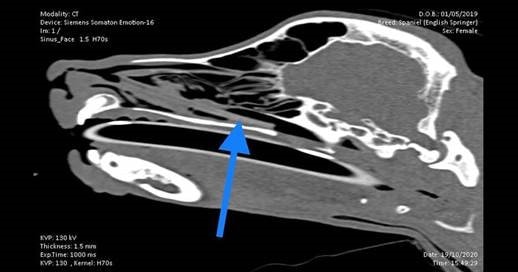

A top vet at one of our northern small animal hospitals has expressed her amazement after retrieving an 8cm stick from the nose of a young springer spaniel.